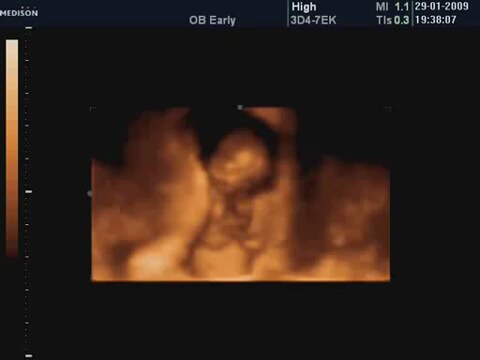

10 Haftalik Bebeğin 4 Boyutlu Ultrason Görüntüsü